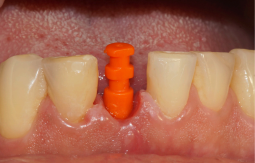

Após esse período, foi selecionado o pilar, e um Pilar Ideale reto de 3.3 X 4.0 X 1.5 mm foi instalado e torqueado a 20 Ncm (Figuras 13 e 14).